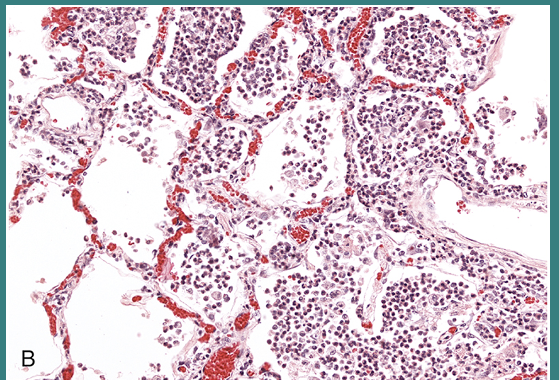

Interstitial fibrosis and chronic inflammatory cells (lymphocytes), interstitial pneumonia